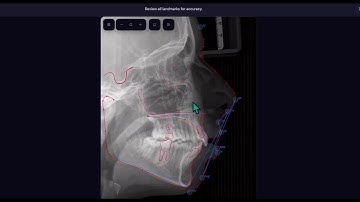

Create cephalometric analysis- Advanced Graphics